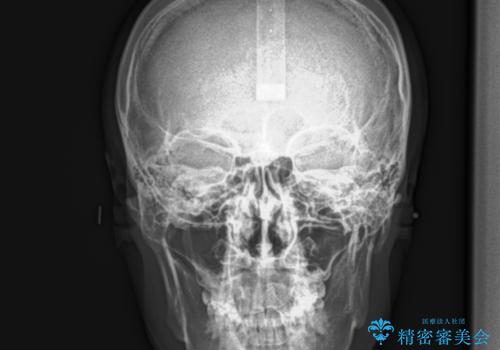

- 30代男性

- 以前、上下左右4本抜いてワイヤー矯正をしていた方で、後戻りで下の前歯のガタガタを気にして来院されました。

マウスピース矯正にて、下の歯はIPR(歯と歯の間を削る)を入れることでガタガタの改善、咬み合わせの深さも改善をはかる治療計画をたてました。